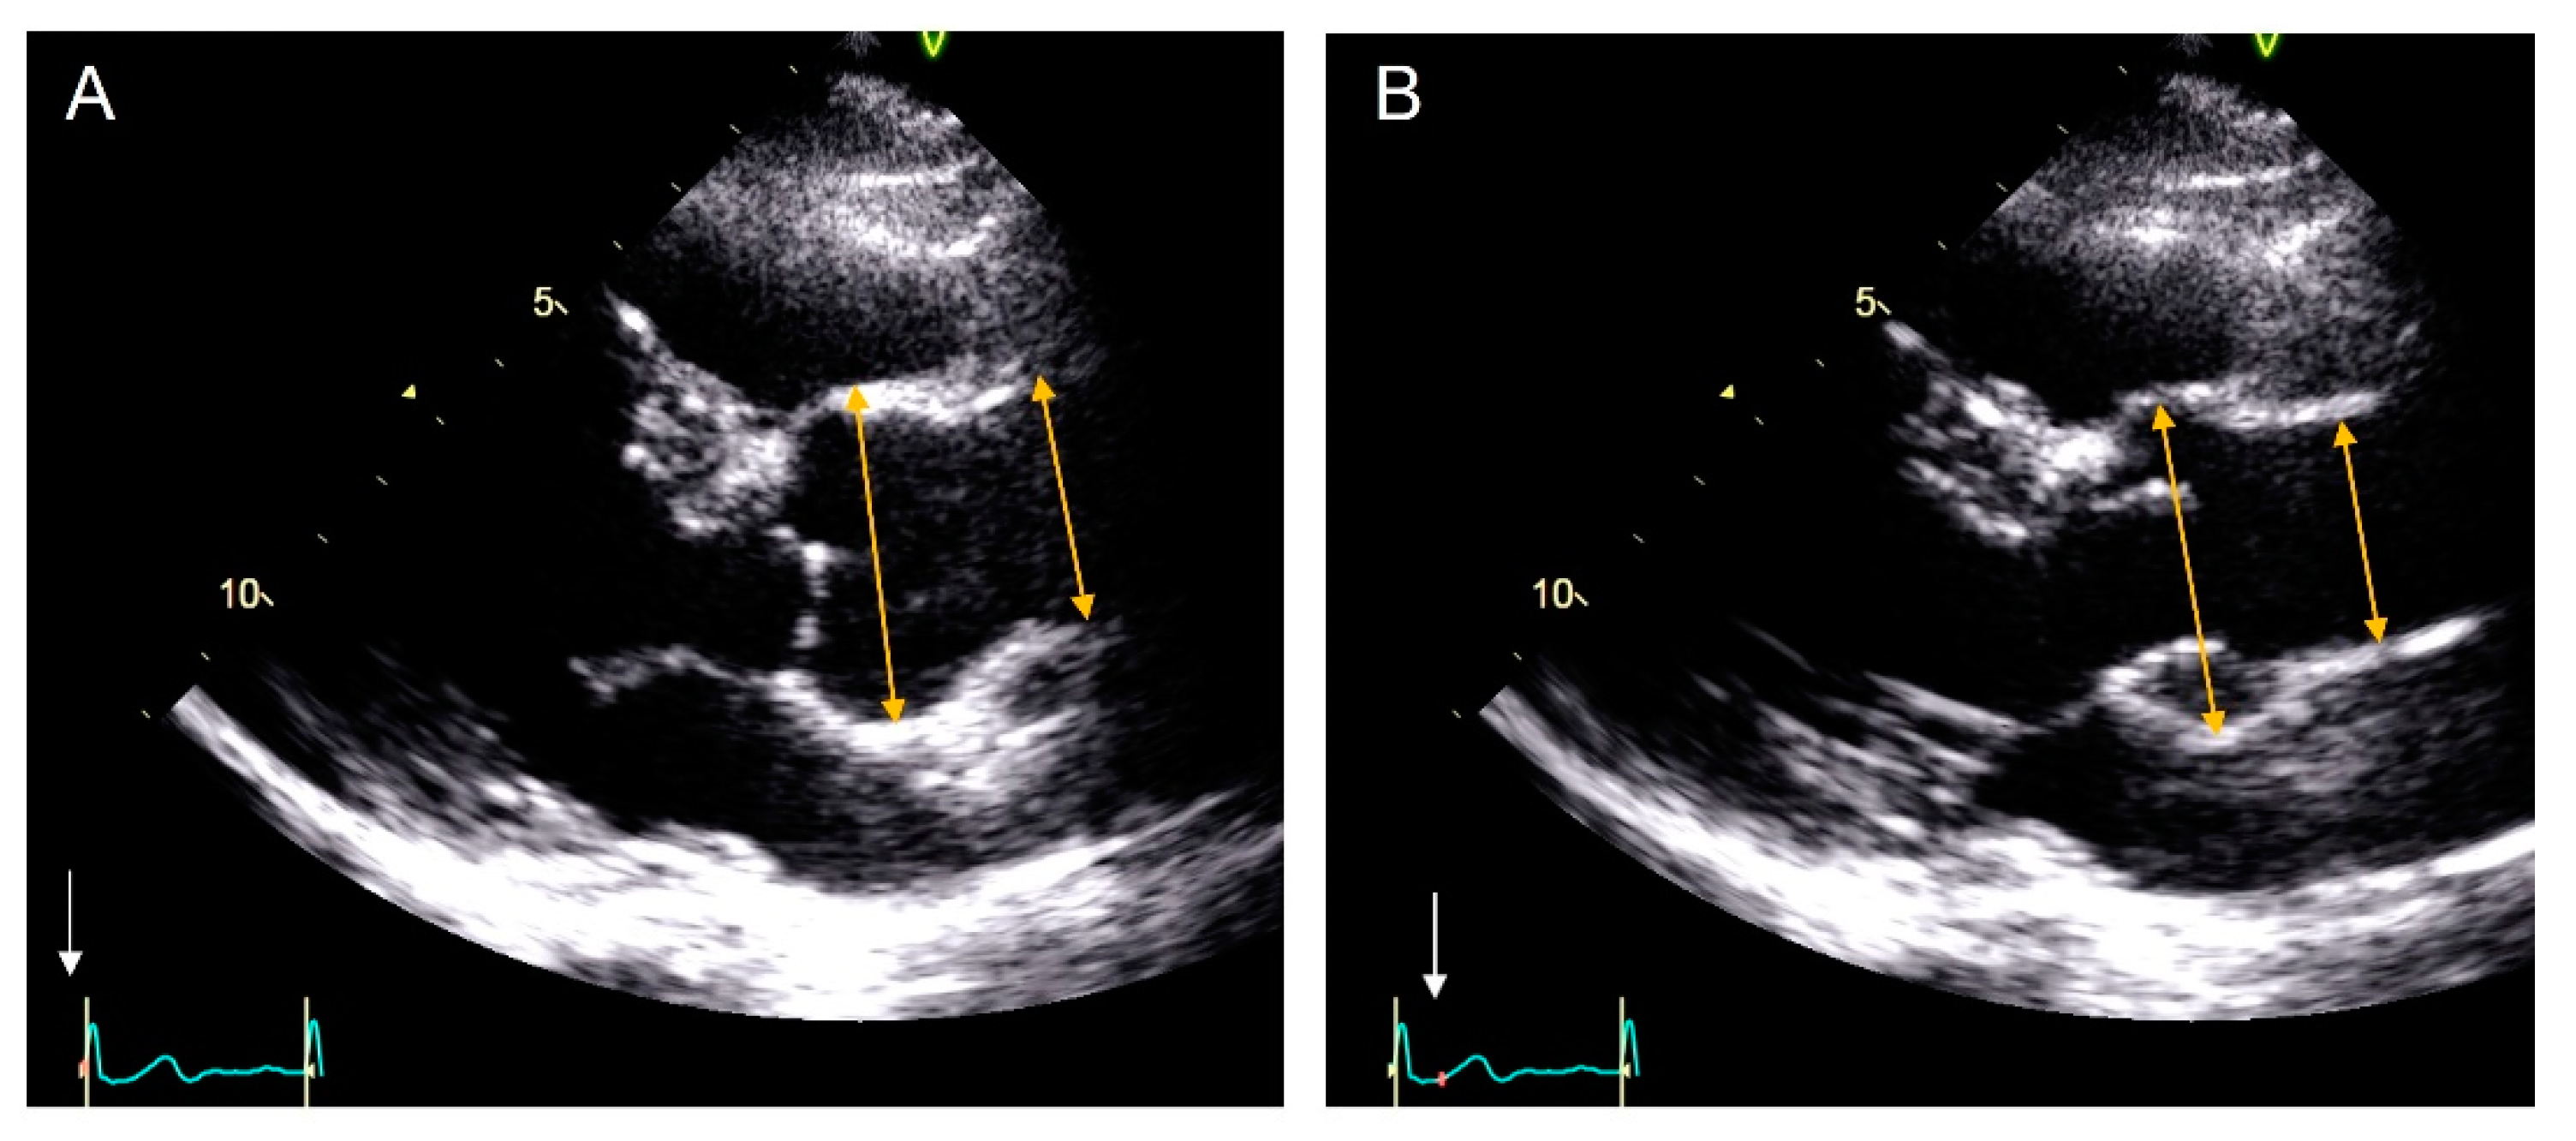

2.1. Echocardiography